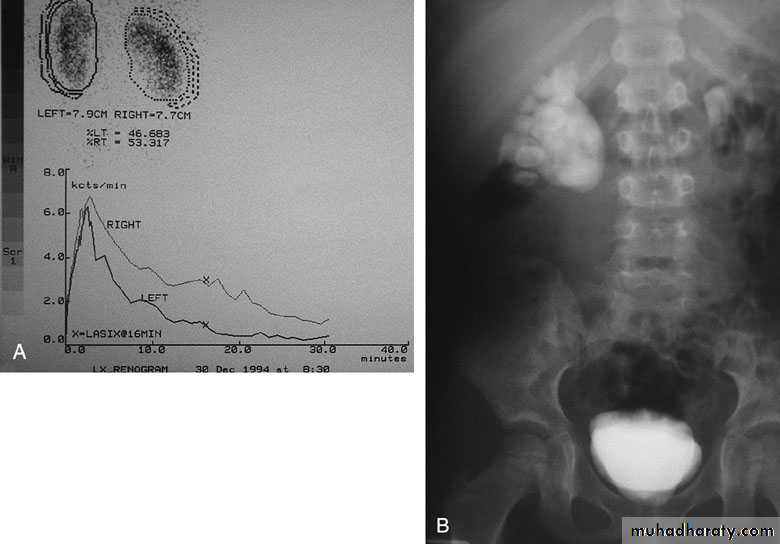

Radionuclide Renography: to see the split function of each kidney

U/S: hydronephrosisIVU: diagnostic , hydronephrosis with fixed stenotic segment or complete obstruction

CT scan: hydronephrosis that ends abruptly